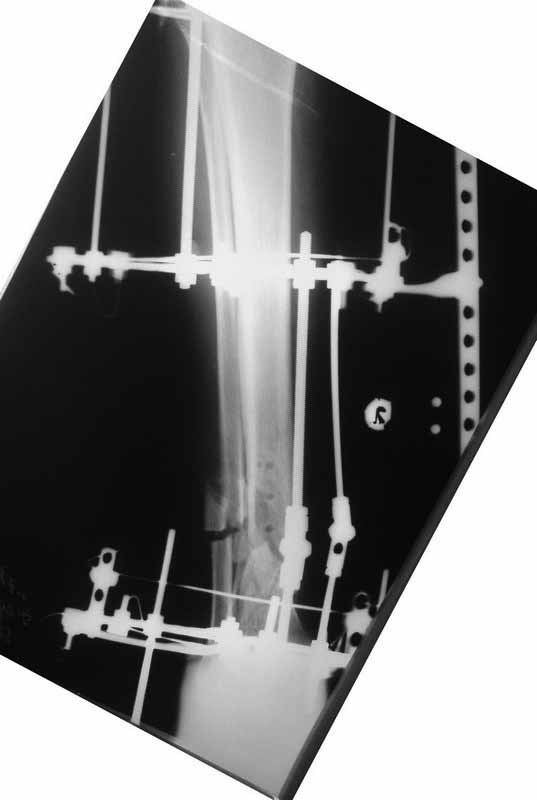

Примерная ситуация. Пациент 37 лет. Синтезировали где-то пластинкой. Попал к нам через 2 месяца.

19 апреля убрали через проколы пластину с винтами, пересекли fibula, наложили аппарат.

Немного потянули по оси, убрали вальгус, ротацию. 22 апреля (на 3-е сутки) заштифтовали окончательно. 29 апреля выписали из отделения. На все ушло 10 дней.